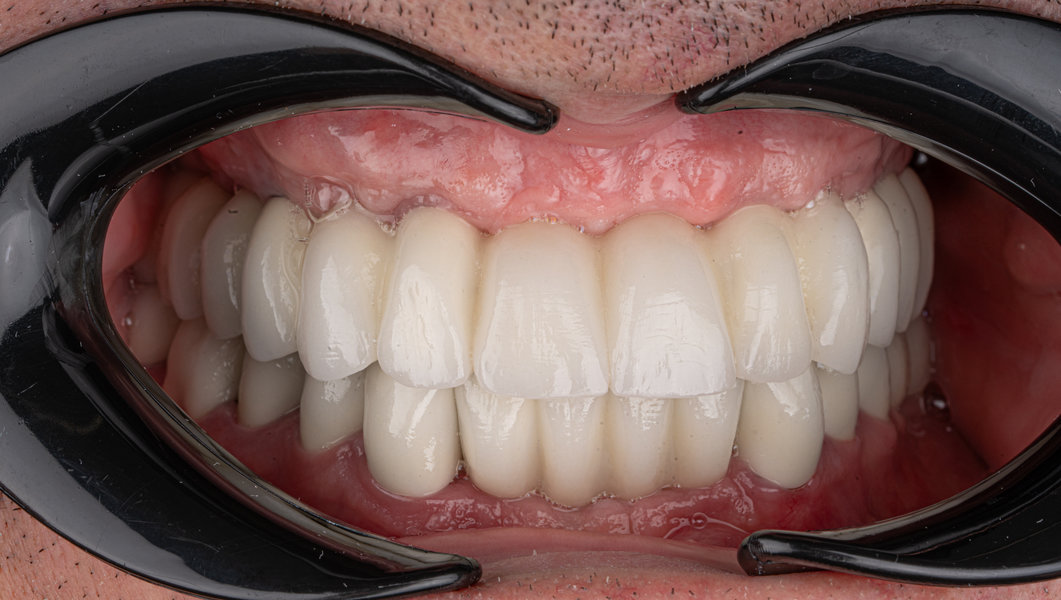

Tomografie (CBCT)

Caz 2